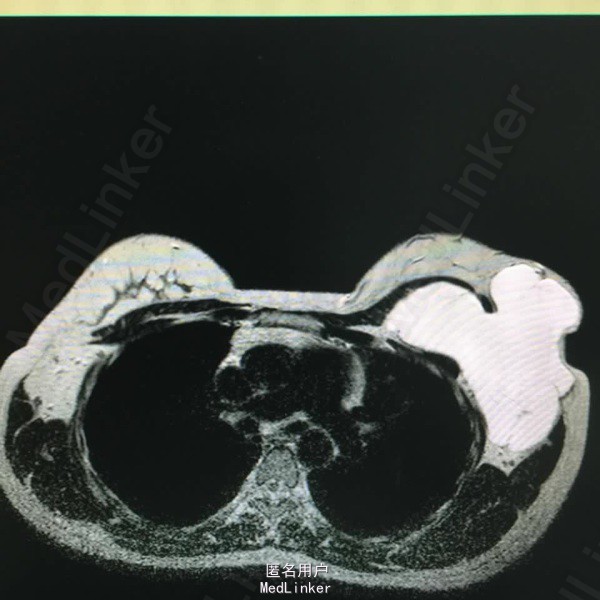

女,28 岁。2年前发现左腋下肿物,近来增大。

左腋下巨大肿物,9厘米。

囊性淋巴管瘤。给予穿刺抽液,注入A组链球菌注射剂。